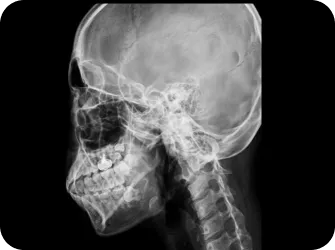

경추 이상 증세

턱관절과 연결된 목뼈 틀어짐을 바로 잡아 얼굴 중심선을 찾으면 자연스럽게 눈썹, 눈, 코, 입이 제자리로 돌아오며 2차 증상도 함께 개선

22개 머리뼈를 바르게

두개천골요법으로

두개골(머리뼈) 교정

1. 턱관절, 목뼈와 함께 틀어진 머리뼈 교정

2. 머리와 목 뒤의 압박을 완화해 교감신경의 긴장을 완화

3. 22개 머리뼈와 나비뼈(눈 구멍을 이루는 뼈, 관자뼈 앞에 위치)

4. 관자놀이, 광대뼈와 근육의 위치 교정

5. 눈과 눈썹의 위치 교정

안면 두개골 엑스레이 검사

안면 두개골 CT

경추 1,2번의 변위 파악